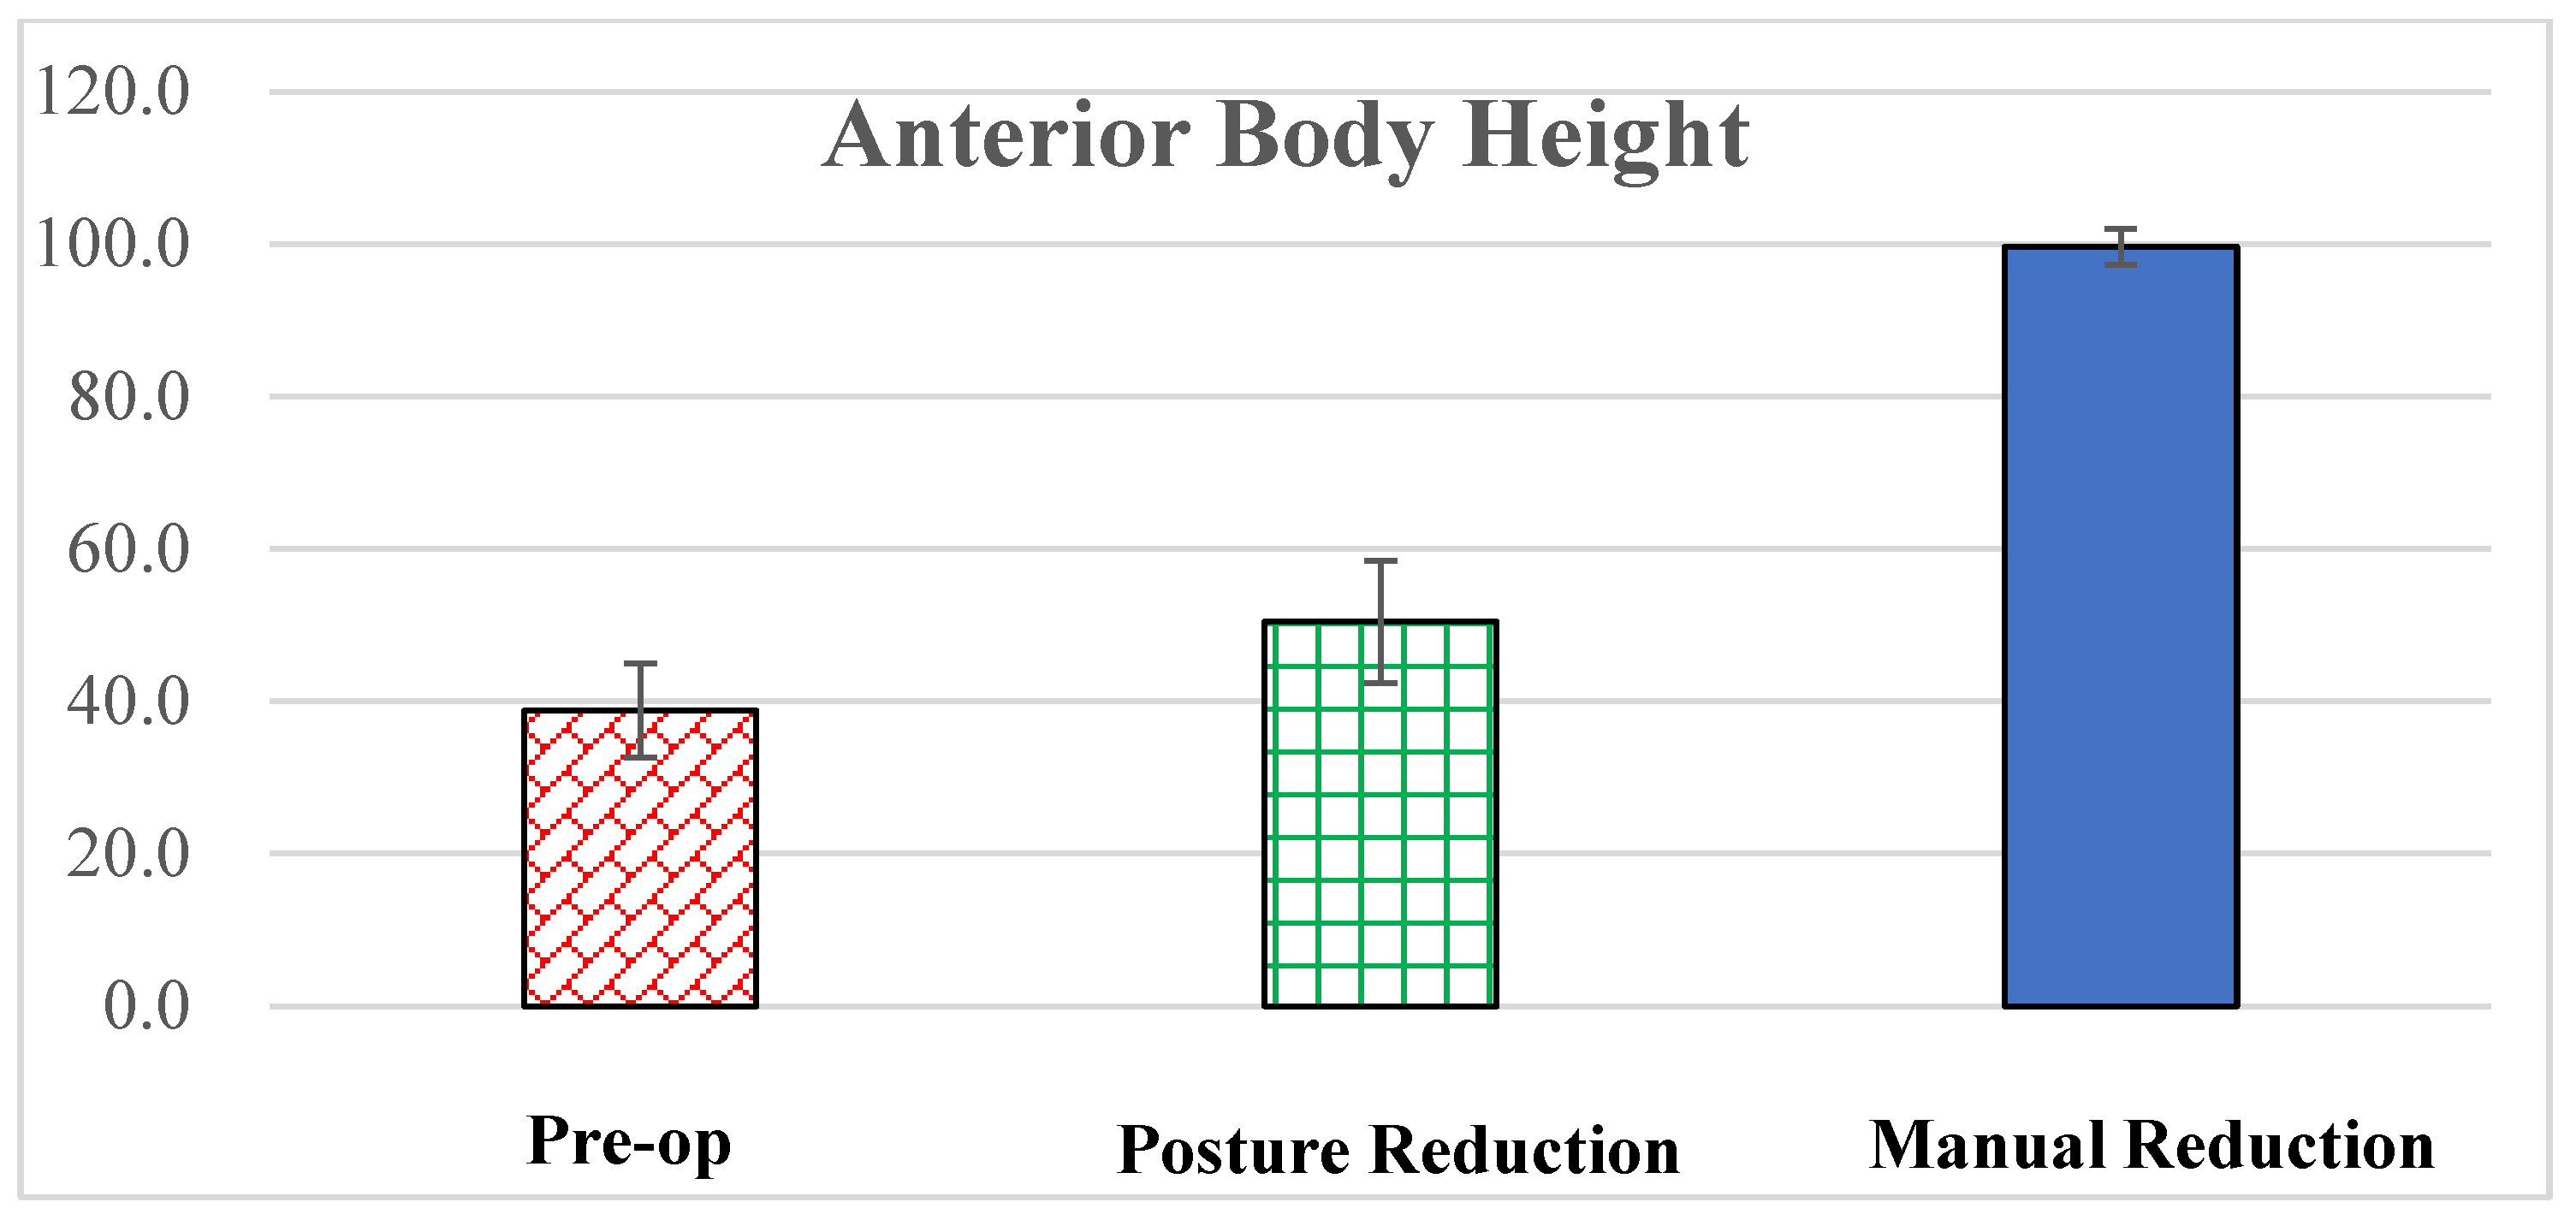

3. Results